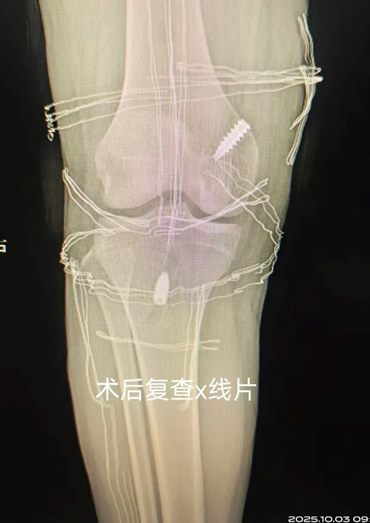

手术由赵意华主治医师与樊彦伟副主任医师共同主刀,在关节镜下微创完成。术中仅做了几个小切口,医生们如同在关节内进行“精工绣花”,将高强度的人工韧带精准植入,重建了膝关节的稳定结构。

由于人工韧带强度远超自体肌腱,固定非常牢靠,为术后早期康复奠定了坚实基础。术后第二天,小王便在支具保护下成功下地站立活动,术后一周,他便顺利康复出院。如此快速的恢复进程,让小王和家人惊喜不已。